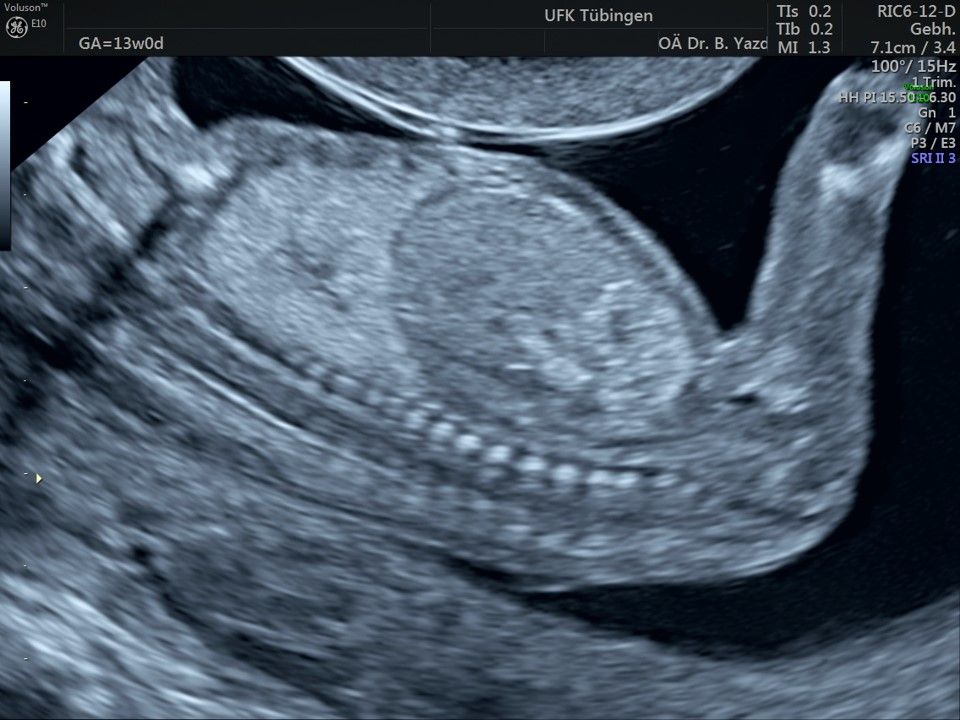

Im Rahmen des Ersttrimester-Screenings untersuchen wir die Organe des Feten mittels Ultraschall. Dabei machen wir auch gerne ein Bild für Sie.

Obwohl der Fet zu diesem Zeitpunkt erst zwischen 5 und 8cm groß ist, lassen sich bereits etwa die Hälfte aller schwerwiegenden Fehlbildungen erkennen bzw. ausschließen. Sollten wir eine Auffälligkeit sehen, werden wir mit Ihnen den Befund und das weitere Vorgehen ausführlich besprechen.

Das Ergebnis der Ultraschalluntersuchung ist wegweisend. Dabei wird der Fet vermessen, die Organe werden untersucht und die sonographischen Marker zur Risikoberechnung für Chromosomenstörungen werden beurteilt. Das sind: die Nackentransparenzdicke, Nasenbein sowie der Blutfluss in der rechten Herzhälfte und im Ductus venosus, einem Gefäß in der Leber des Feten.